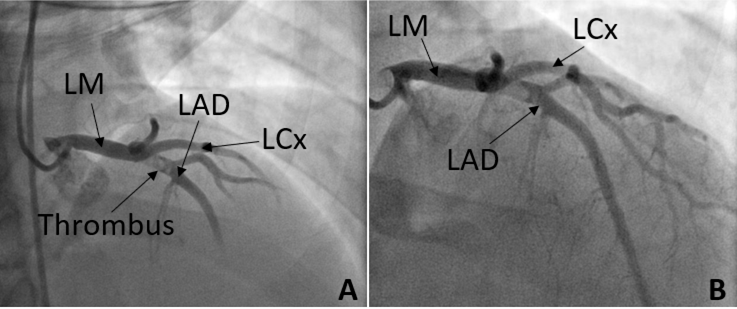

At the outside hospital, the patient was hemodynamically stable, and the initial electrocardiogram (ECG) showed anterolateral ST-segment elevation concerning for STEMI. He was therefore transferred to a percutaneous coronary intervention-capable facility. Repeat ECG on arrival demonstrated ST-segment elevation in leads II, III, aVF, and V2–V6 (Figure 1). High-sensitivity troponin was elevated to 1,130 pg/mL, and the patient underwent emergent coronary angiography. Angiography demonstrated a large filling defect in the proximal left anterior descending artery (pLAD), consistent with thrombus, with TIMI 1 flow (Figure 2). Aspiration thrombectomy was partially successful, leaving residual stenosis but restoring TIMI 3 flow. The patient was treated with aspirin, ticagrelor, atorvastatin, and a tirofiban infusion for 24 hours because of the heavy thrombus burden.

Figure 2. A. Left Heart Catheterization showing LAD with presence of thrombus in the proximal segment. B. Left Heart Catheterization showing LAD immediately after aspiration thrombectomy and intracoronary adenosine administration.